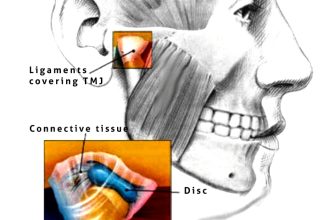

Have you ever experienced limited neck movement or

Lockjaw, also known as temporomandibular joint disorder